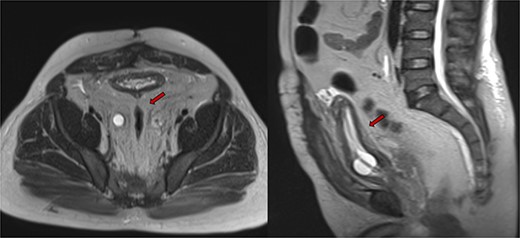

Abdominopelvic MRI T2-weighted imaging demonstrated severe bilateral hydroureteronephrosis (Fig. 1, yellow arrows) with thinning of the right renal cortex (blue arrow), suggestive of chronic obstruction.

Abdominopelvic MRI T2WI demonstrating severe bilateral hydroureteronephrosis (yellow arrows) with thinning of the right renal cortex (blue arrow).